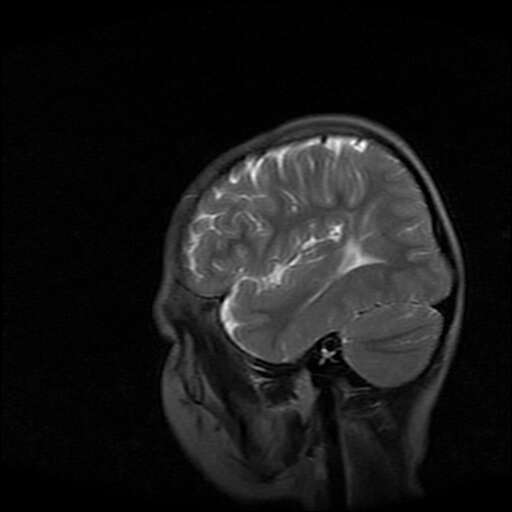

女,7岁,三岁才说话、走路。现智力尚可,走路不稳。临床怀疑大脑发育不全。

脑折质变薄,双侧侧脑室稍扩张,支持考虑脑折质发育不良

考虑胼胝体发育不全,髓鞘形成不良。

支持考虑胼胝体发育不全,髓鞘形成不良。

侧脑室周围白质数量减少,侧脑室不对称性扩大,左侧侧脑室后角呈方形改变,脑沟加深,结合临床考虑脑室周围白质软化症(pvl)。期待结果!

支持脑白质发育不良。